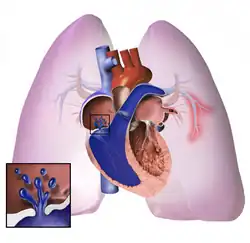

Right ventricle (on left side)

The pathogenesis of pulmonary arterial hypertension (WHO Group I) involves the narrowing of blood vessels connected to and within the lungs. This makes it harder for the heart to pump blood through the lungs, as it is much harder to make water flow through a narrow pipe as opposed to a wide one. Over time, the affected blood vessels become stiffer and thicker, in a process known as fibrosis. The mechanisms involved in this narrowing process include vasoconstriction, thrombosis, and vascular remodeling (excessive cellular proliferation, fibrosis, and reduced apoptosis/programmed cell death in the vessel walls, caused by inflammation, disordered metabolism and dysregulation of certain growth factors).[27][28] This further increases the blood pressure within the lungs and impairs their blood flow. In common with other types of pulmonary hypertension, these changes result in an increased workload for the right side of the heart.[16][29] The right ventricle is normally part of a low pressure system, with systolic ventricular pressures that are lower than those that the left ventricle normally encounters. As such, the right ventricle cannot cope as well with higher pressures, and although right ventricular adaptations (hypertrophy and increased contractility of the heart muscle) initially help to preserve stroke volume, ultimately these compensatory mechanisms are insufficient; the right ventricular muscle cannot get enough oxygen to meet its needs and right heart failure follows.[16][28][29] As the blood flowing through the lungs decreases, the left side of the heart receives less blood. This blood may also carry less oxygen than normal. Therefore, it becomes harder and harder for the left side of the heart to supply sufficient oxygen to the rest of the body, especially during physical activity.[30][31][11] During the end-systolic volume phase of the cardiac cycle, the Gaussian curvature and the mean curvature of the right ventricular endocardial wall of PH patients were found to be significantly different as compared to controls.[32]